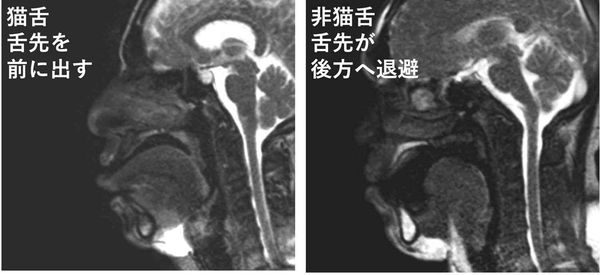

下の画像の左側が“猫舌群”、右が“非猫舌群”だ。 猫舌ではない人の場合、お茶が口に入ると舌が後方に移動して、下の歯と舌の間に“ポケット”を作り、そこにお茶を溜めている。そのあとで舌の周囲を伝ってのどへと流し込んでいくのだ。 一方の猫舌の人は、まず最初に舌先をお茶に接することからスタートする。非猫舌群の人が終始舌先をお茶に接しないようにしているのとは正反対の動きだ。 熱いものを食べる時には意識的に舌は奥へと引っ込め、舌の下のポケットに一旦収めるようにトレーニングすればいいのだ。熱いものが食べられない……「猫舌」を徹底的に研究してわかった“そうでない人”の決定的な違い | 文春オンライン